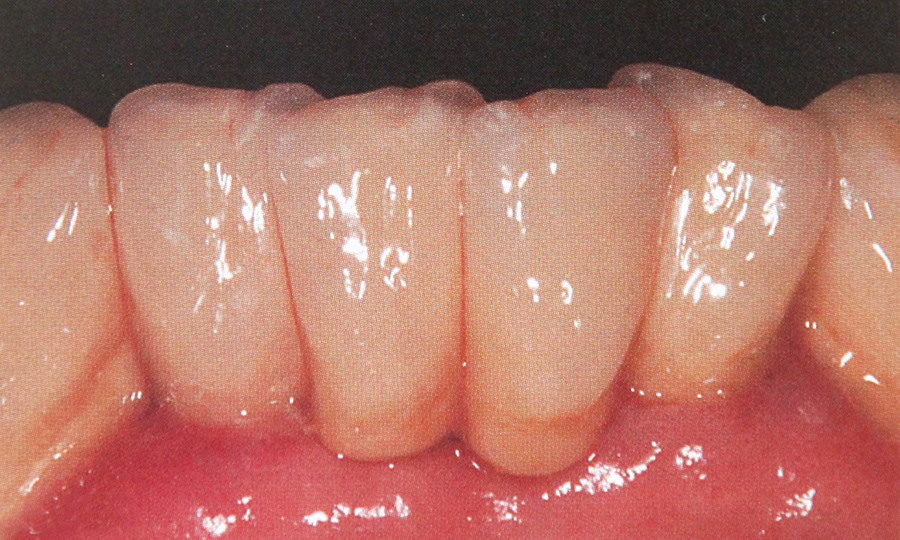

Tehnicile adezive directe de lucru cu materiale bazate pe rasini composite reprezinta o modalitate excelenta de restaurare estetica si minim invaziva a dintilor frontali. Obtinerea rezultatelor estetice asteptate este legata indesolubil de alegerea si utilizarea corecta, conform indicatiilor, a materialelor si tehnicilor de lucru adecvate, fiecarei situatii clinice.